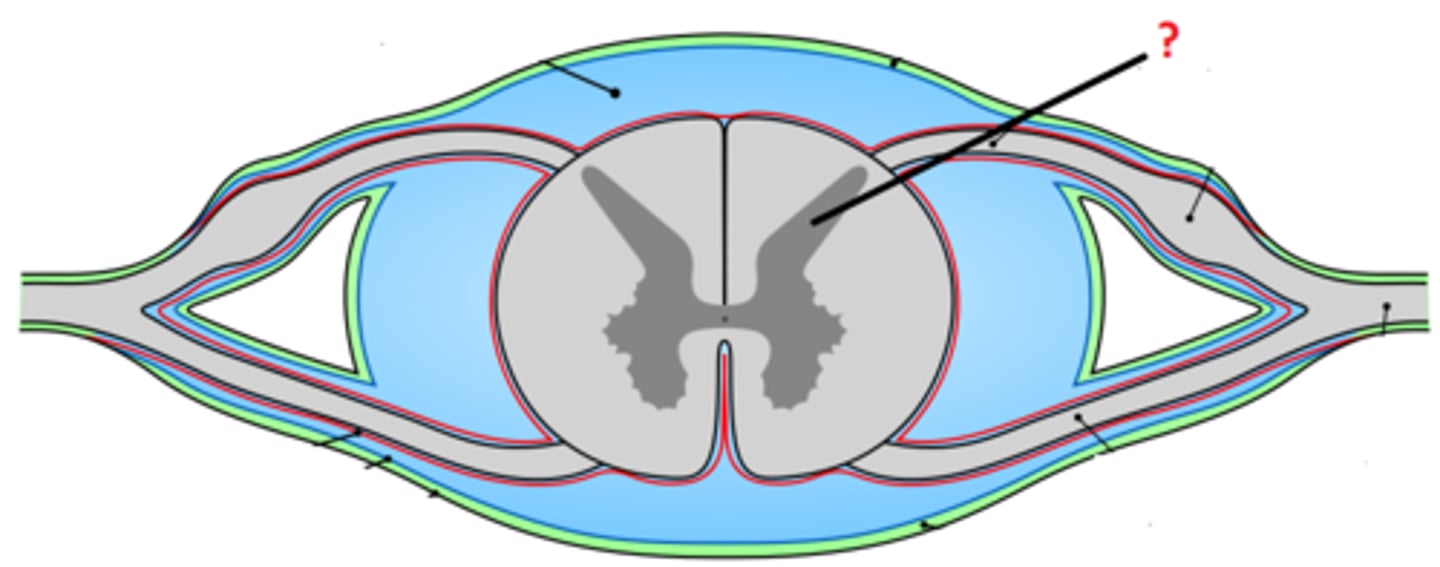

arachnoid mater

dura mater

denticulate ligament

pia mater

subdural space

epidural space

subarachnoid space